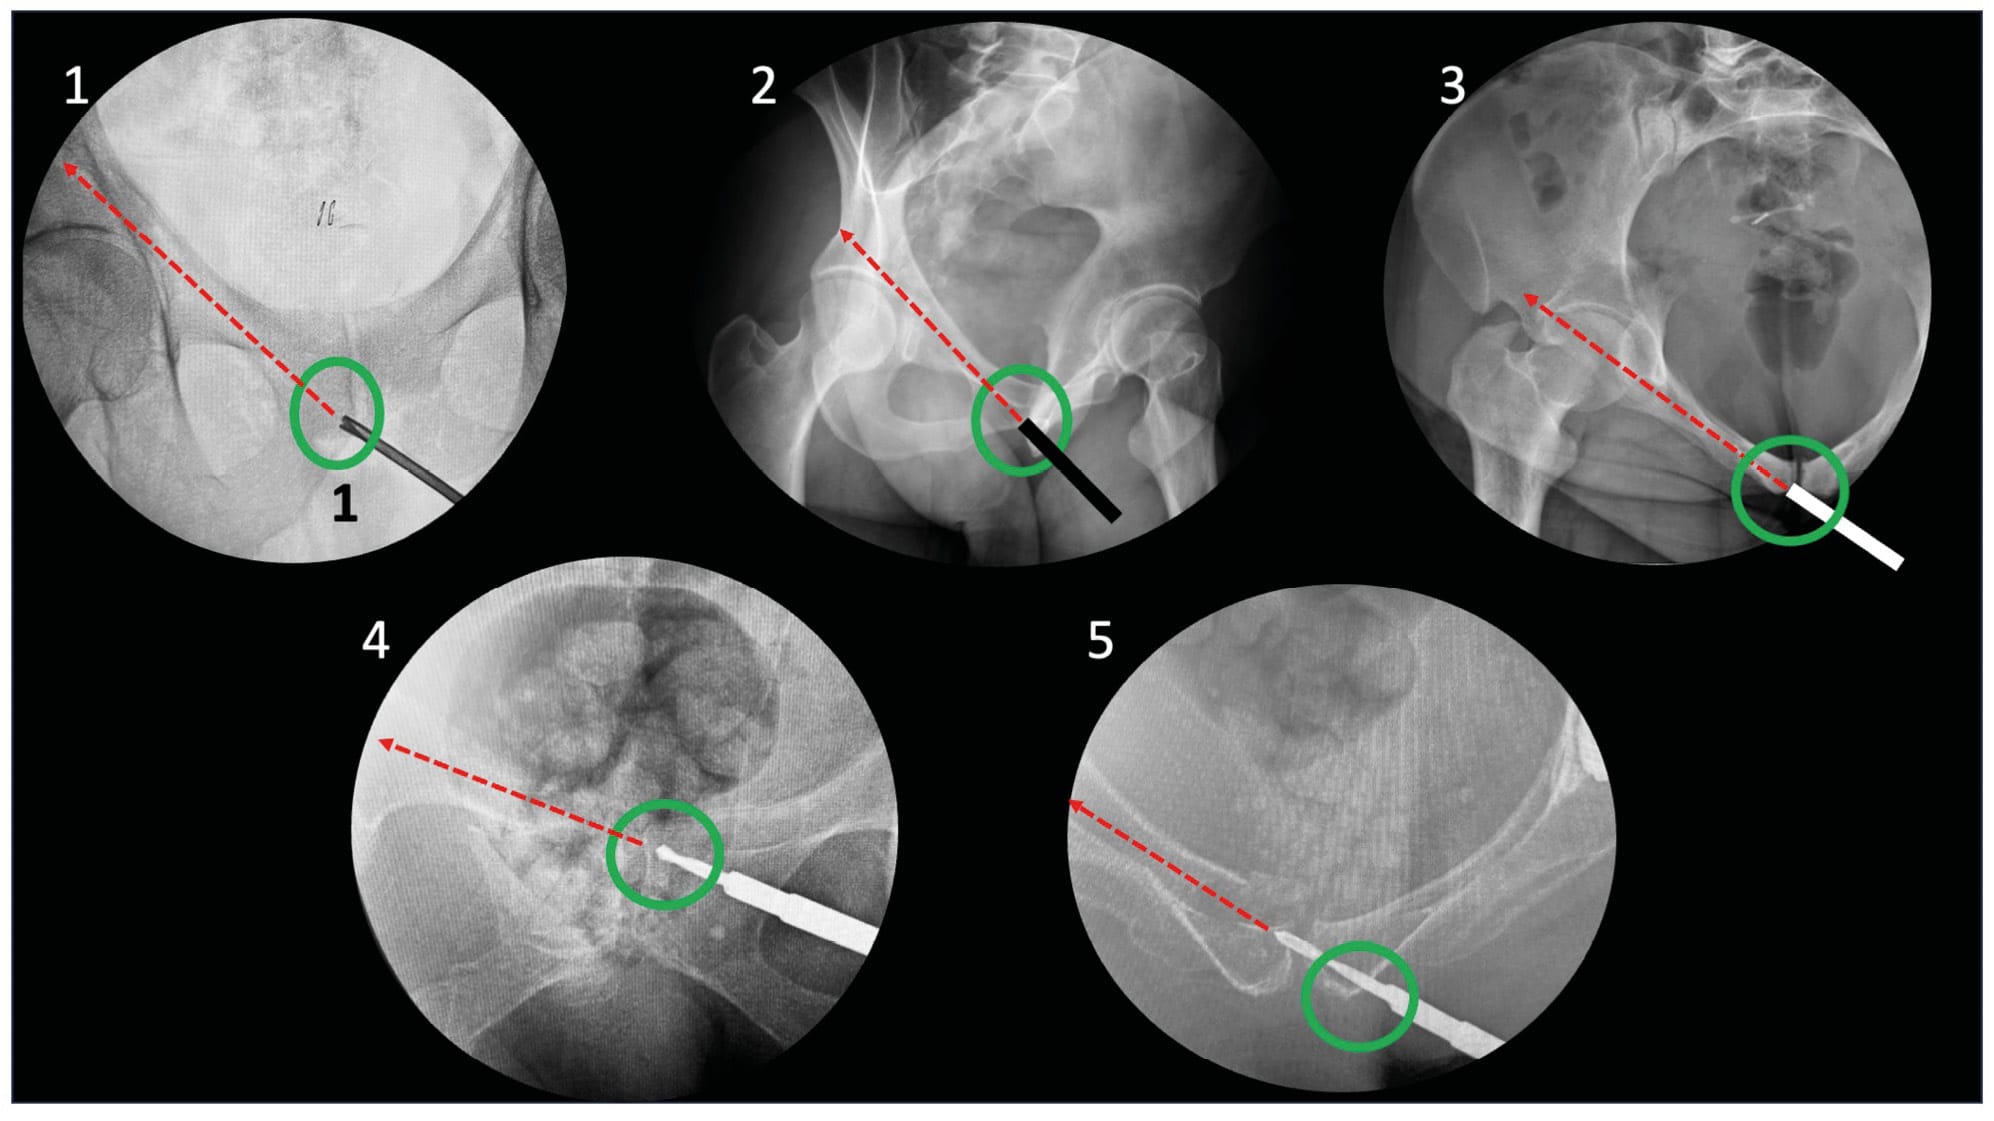

In this technique, the patient is positioned supine with the sacrum elevated on a cushion. Similar to anterior column (AC) screw fixation, there are antegrade and retrograde approaches. The antegrade fixation is not truly "percutaneous" as it requires a small iliac approach. However, retrograde fixation is performed using the classic percutaneous method. A high posterior column fracture will more readily accommodate antegrade fixation, while a fracture in the lower portion of the column is better suited for retrograde fixation, although both techniques are equivalent.

For the surgical field, it is necessary to include the ipsilateral lower limb during retrograde fixation, taking care to exclude the external genitalia. This allows positioning of the ischial tuberosity in the surgical field when the assistant places the hip in deep flexion. The image intensifier is positioned facing the surgeon.

Regarding imaging views, this technique requires an anteroposterior view, obturator oblique view, and iliac oblique view. The anteroposterior and obturator oblique views are used to guide the guide wire toward the ischial tuberosity. The iliac oblique view helps verify that the wire remains clear of the hip joint and the greater sciatic notch. The obturator oblique view ensures the wire is not medial to Kohler's line, i.e., intrapelvic. (Figure 3)

For antegrade fixation, a small approach is necessary. This involves a mini-window in the iliac portion of the ilioinguinal approach. To obtain the best trajectory without soft tissue interference, a 2 cm skin incision is made, starting 4 fingerbreadths from the anterior superior iliac spine (ASIS). The iliacus muscle is subperiosteally stripped along the internal table of the innominate bone. The entry point is located approximately 2 cm lateral to the pelvic brim. The direction is obtained using the radiographic views. The use of a percutaneous trocar is imperative to preserve skin integrity and allow support against the thoracic cage to prevent guide wire bending.

For retrograde fixation, the hip is placed in deep flexion with the knee flexed, and the entry point is located in the medial half of the ischial tuberosity. Here too, percutaneous reduction techniques are described, but the difficulty in achieving perfect articular reduction leads to favoring this option for minimally or non-displaced fractures, or as a complement to conventional open osteosynthesis. Once the guide wire is in place and after verifying the absence of false passages on different views, measurement is performed. A lateral view may be useful for evaluating length, particularly in retrograde fixation. Indeed, the cortical density line of the innominate bone indicates the wire's exit point. A 6.5- or 7.3-mm screw is typically used, with partial or full threading depending on the fracture pattern and proximity to the joint (Figures 9 and 15).